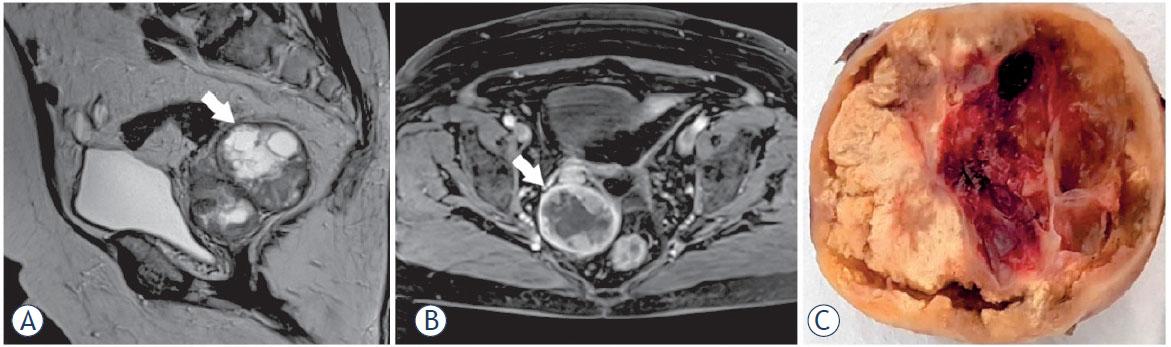

Figure 2